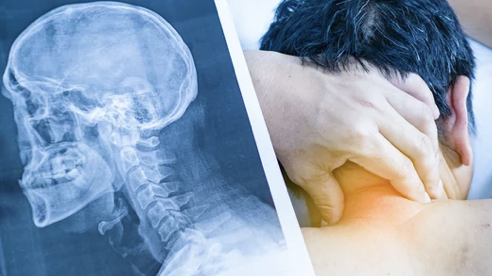

목디스크는 목뼈 사이의 디스크가 탈출하여 신경을 압박할 때 발생하는 질환입니다. 이는 흔한 질환으로, 모든 연령대에 영향을 미칠 수 있지만 30~50대 사이에서 가장 흔합니다. 오늘은 목디스크 증상과 치료방법, 베개, 견인치료기, 운동 등 목디스크에 대한 다양한 정보를 알려드리겠습니다.

목디스크는 목뼈 사이의 디스크가 탈출하여 신경을 압박할 때 발생하는 질환입니다. 목 뒤 통증, 어깨 통증, 팔 저림, 근력 약화 등의 증상을 유발할 수 있습니다.